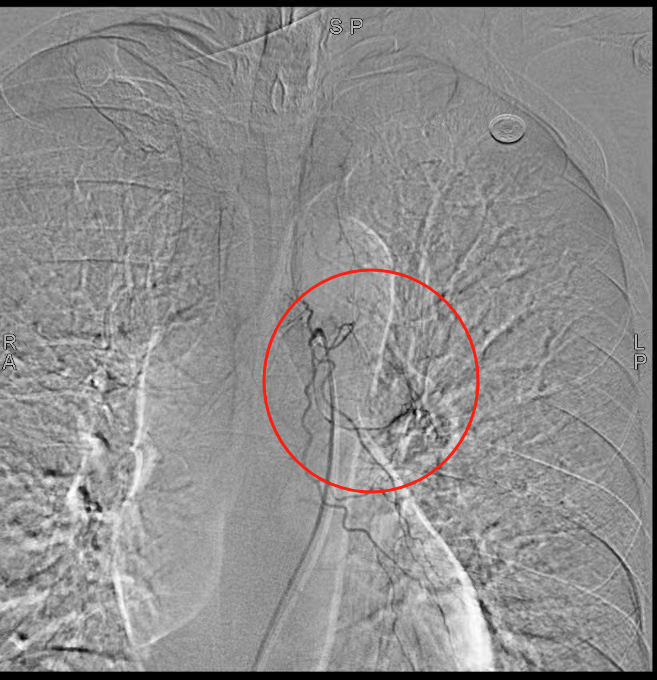

1.血管介入止血:通過支氣管動脈栓塞術(shù)緊急控制出血風(fēng)險(xiǎn);